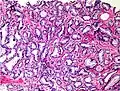

Gleason pattern 4. H&E stain.

• Pattern 4 - The tissue has few recognizable glands. Many cells are invading the surrounding tissue in neoplastic clumps. This corresponds to a poorly differentiated carcinoma.

Gleason pattern 4 glands are no longer single/separated glands like those seen in pattern 1-3. They look fused together, difficult to distinguish, with rare lumen formation vs Gleason 1-3 which usually all have open lumens (spaces) within the glands, or they can be cribriform-(resembling the cribriform plate/similar to a sieve. An item with many perforations). Fused glands are chains, nests, or groups of glands that are no longer entirely separated by stroma-(connective tissue that normally separates individual glands in this case). Fused glands contain occasional stroma giving the appearance of "partial" separation of the glands. Due to this partial separation, fused glands sometimes have a scalloped (think looking at a slice of bread with bite taken out of it) appearance at their edges.[3][6]